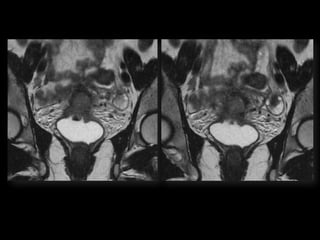

HISTORY โ€ข 42 yo female โ€ข Recent immigrant from China โ€ข C/O postcoital and intermenstrual bleeding โ€ข Abnormal GYN exam โ€ข Abnormal biopsy โ€ข Further imaging performed

MRI findings -Stage IIB with PET/CT - Stage IIIB Cervical Cancer

Stage I โ€“Carcinoma Confined to Cervix <= 4 cm greatest dimension > 4 cm greatest dimension <= 7 mm wide A1 < =3mm deep A2 >3 but < 5mm deep

Stage II โ€“Carcinoma Invades Beyond Uterus But not to Pelvic Wall or Lower 1/3 Vagina With(A) or without (B) parametrial invasion

Stage III โ€“Carcinoma to Pelvic Wall and/or Lower 1/3 of Vagina and/or Causes Hydronephrosis or Nonfxing Kidneys Lower 1/3 Vagina No pelvic wall Extends to pelvic wall and/or renal issues

Stage IV โ€“Carcinoma beyond True Pelvis or Involvement Of Mucosa of Bladder or Rectum (bx proven) Distant Mets Spread to adj organs

Role of MRImaging in Tx Stratification of GYN (Cervical) Cancer โ€ข Cervical Cancer โ€“ 2nd most common ca in women worldwide โ€“ Developing countries; pk 30-40 yrs โ€ข FIGO classification โ€“ revised in 2009 from just clinical to incorporate cross-sectional imaging (CT, MR) โ€ข Staging accuracy of MR 85-96% โ€“ Best test to assess tumor size and location; invasion into parametria, pelvic side wall, adjacent organs; local nodal enlgment โ€ข PET/CT helpful in staging advanced disease โ€“ Demonstrates unexpected sites beyond pelvis โ€ข Treatment options โ€“ Radical surgery - early stage (IA, IB1, IIA1) โ€“ Primary Chemo and Radiation โ€“ bulky IB2 or IIA2, or local advanced (IIB or greater) Sala et al. Radiology 2013; 266: 717.